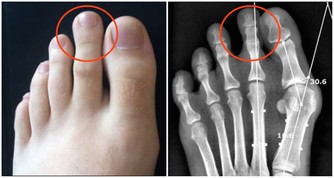

在晚上睡覺的時候,有不少的人出現了腿腳抽筋的現象,大部分的人都認為這種現像只是因為缺鈣引起的,

實際上,缺鈣是一種原因,當我們血液中的鈣濃度下降時,

進而就會引起神經肌肉的興奮性加強,這種現像從專業的角度叫作肌肉痙攣,

而往往最典型的表現就是腿腳抽筋,不管是夜晚還是在白天,都有可能出現。

這時候就需要我們日常的補些鈣片了,進而讓我們的血液中不再缺少鈣的成分,

但除了這種缺鈣的情況,腿腳抽筋還可能是以下這幾種原因,別大意!